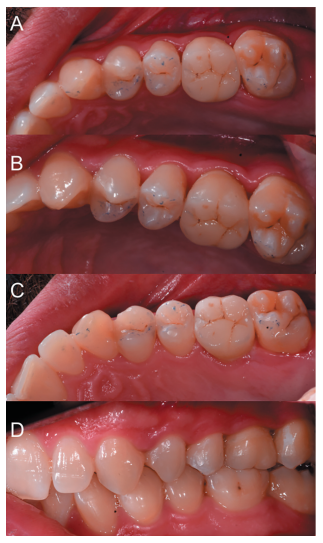

Caso clínico: se presenta el caso de un varón de 28 años, que acudió a consulta por la presencia de unos restos radiculares en localización de primer molar superior izquierdo. Se realizó un autotrasplante dental, siendo el diente donante el tercer molar superior izquierdo, que se trasplantó al alveolo del primer molar, mostrando buena evolución clínica y radiográfi ca.

Clinical case: a clinical case of a 28-yearold man is presented, who went to dental clinic for removal of left fi rst molar roots. An autotransplant was performed using left third molar as donor tooth, which was transplanted into fi rst molar alveolus, showing promising clinical and radiographic evolution.

Por tanto, debido a las altas tasas de éxito descritas en la literatura, el objetivo del presente caso clínico es evaluar clínica y radiográficamente la realización de un autotrasplante con el ápice cerrado, para reponer un primer molar superior izquierdo, como alternativa terapéutica a la colocación de un implante en un paciente adulto.